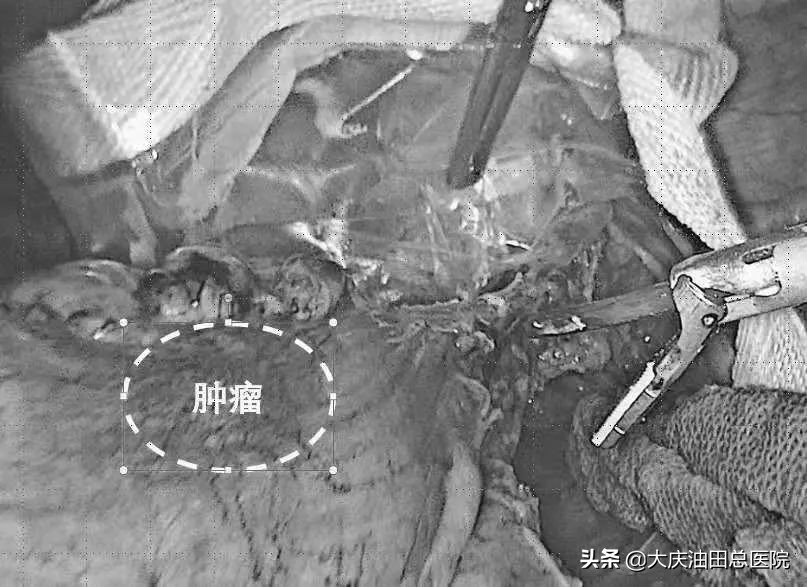

肠镜检查:距肛门8cm见不规则肿物,表明呈菜花状,质脆

重点:切除了这么大的肿瘤,没在患者腹部开辅助切口

(为了你的眼睛,图片已技术处理)